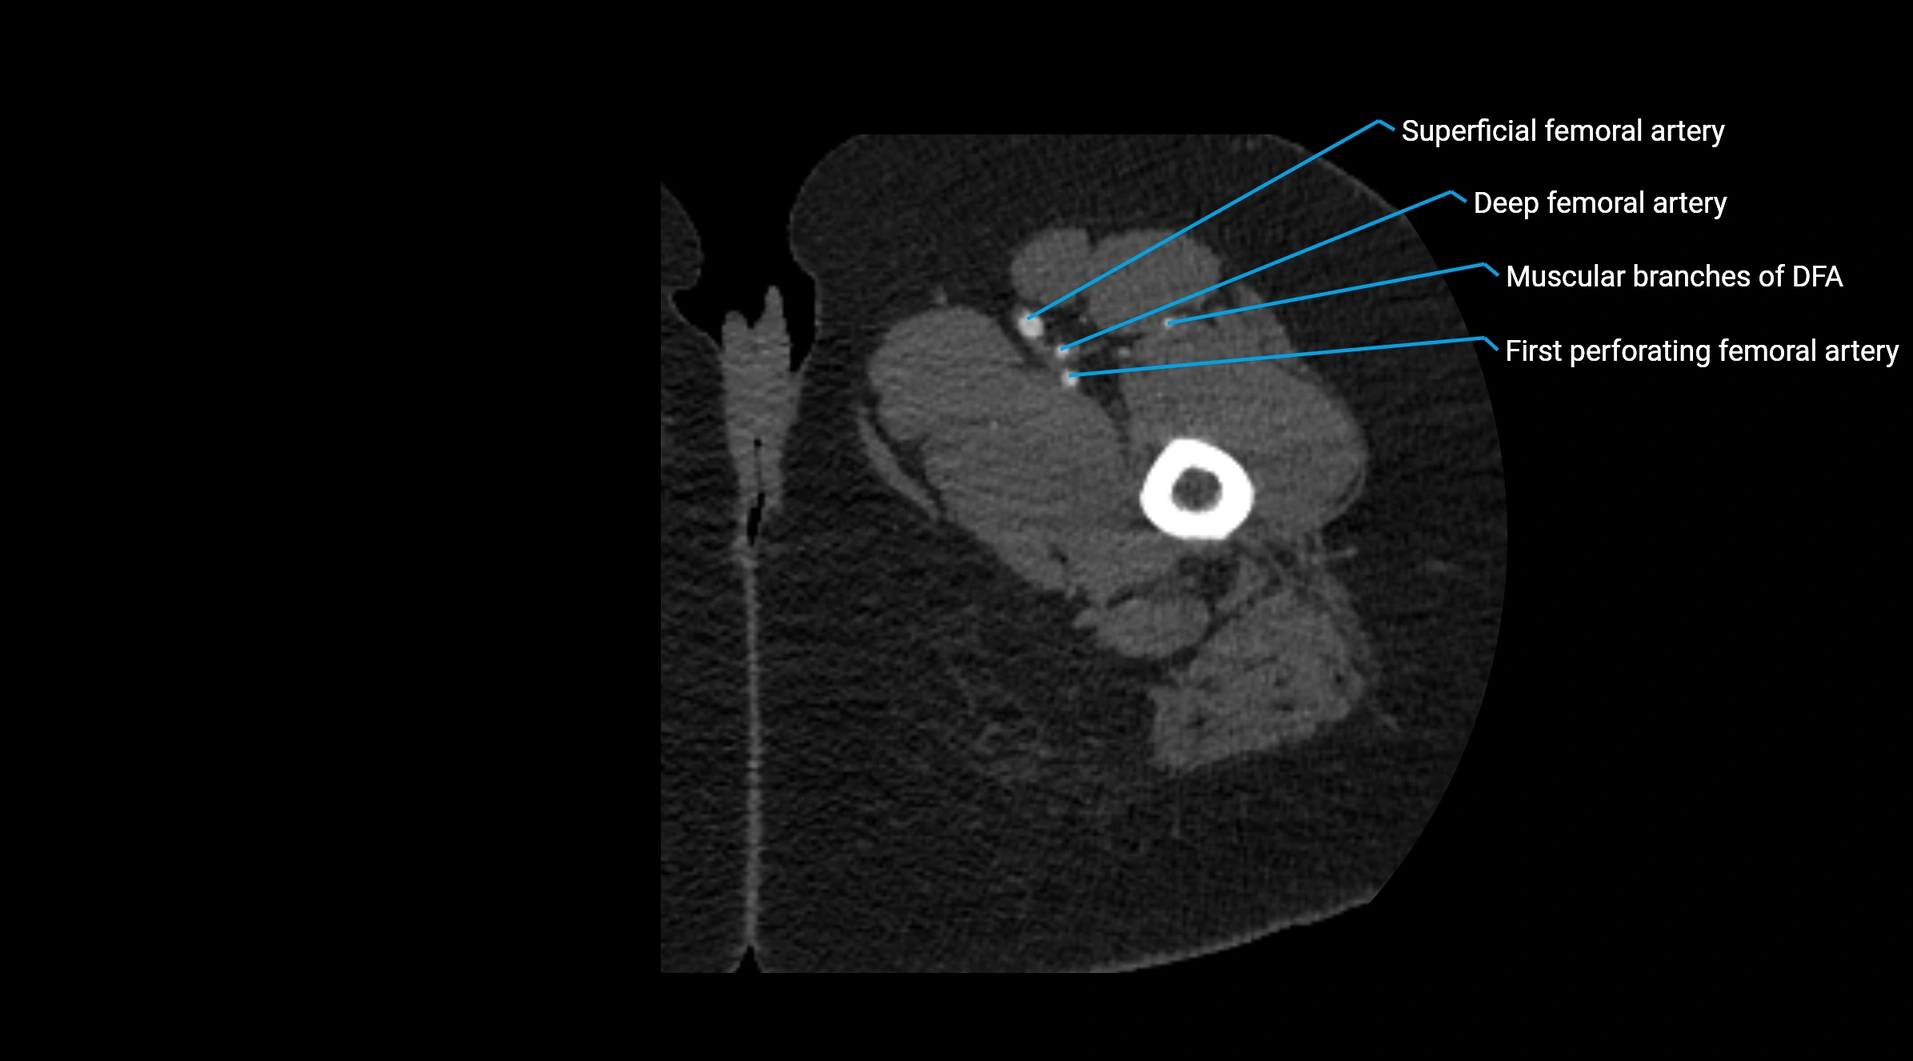

Contrast-enhanced CT (CTA):

• Gold standard for abdominal aortic imaging

• Provides excellent detail of lumen, wall, aneurysm, thrombus, and branch vessels

• Multiplanar and 3D reconstructions help in aneurysm measurement, stent graft planning, and dissection evaluation